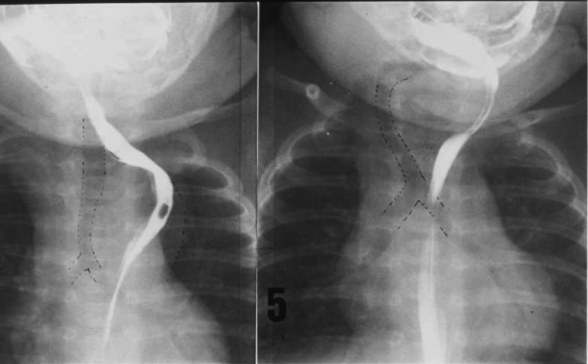

- Type Ia : stenose distal effilee

- Type Ib : stenose distal "abrupte

"

- Type II :

flammeche ( flash-shape shadow )

- Type III

: Comme type I , II avec extravation de

radio-opaque a hauteur de la stenose

Image

radiologique de deux type de stenose oesophgienne

congenitale 1a, 2 et 1b en fusiforme , en flammeche

et abrupte |

|

Stenose

congenitale oesophagienne avec oesophagite

peptique(RGO). Oesophage en achalasia . |